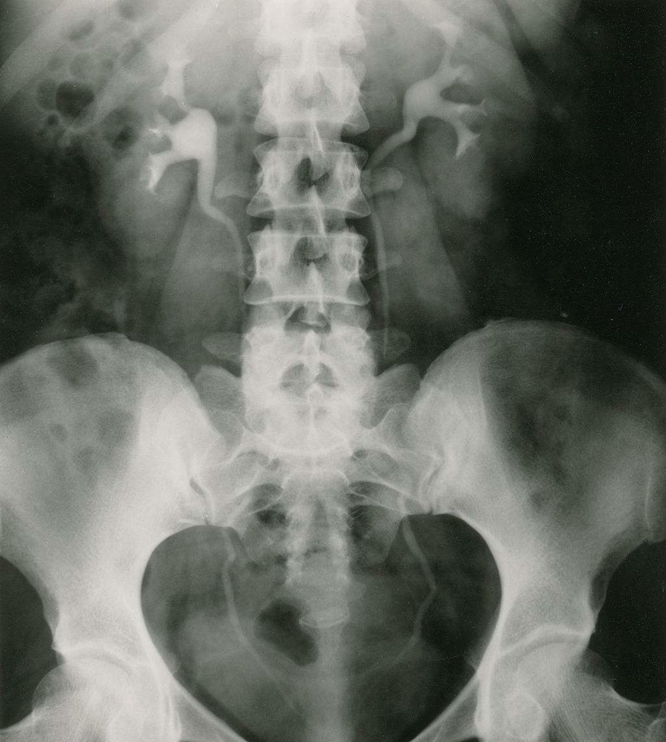

腹部平片:是泌尿系統(tǒng)常用的檢查方法; 常規(guī)攝取仰臥前后位片。

泌尿系結(jié)石:約90%結(jié)石可由線平片顯示,稱為陽(yáng)性結(jié)石;如尿酸鹽結(jié)石難在平片上顯示,稱為陰性結(jié)石。腎結(jié)石可為單側(cè)或雙側(cè)性,影像技術(shù)中表現(xiàn)為圓形、卵圓形、桑椹狀、鹿角狀或不定形密度增高陰影;密度可均勻、不均勻或分層狀。大多發(fā)生在腎盞或腎盂部位,可單發(fā)或多發(fā)。輸尿管結(jié)石多由腎結(jié)石移行而來(lái),較小的米粒到黃豆大小,大的桑椹或棗核狀大?。婚L(zhǎng)軸與輸尿管走行一致,常見(jiàn)于生理狹窄處。